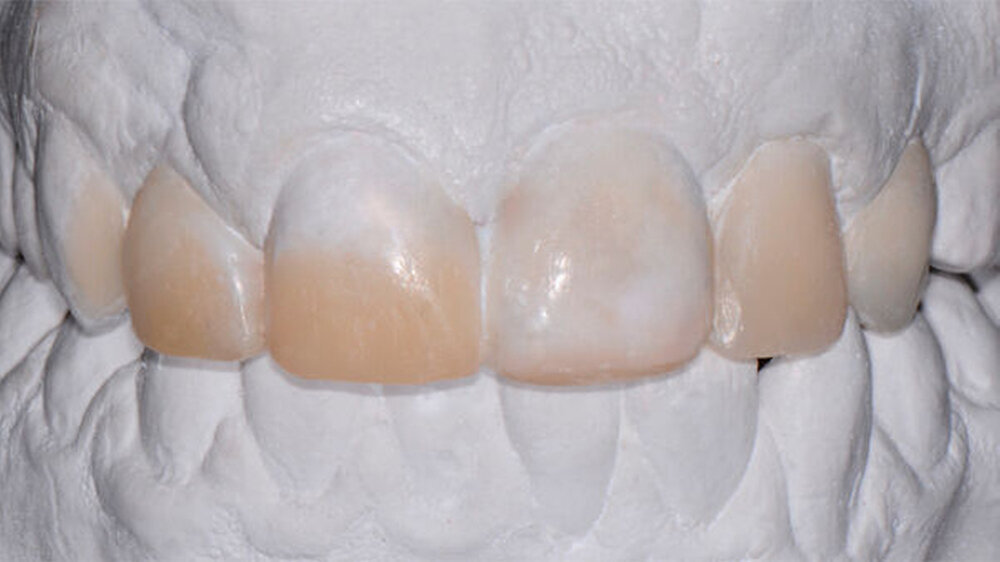

Bei diesem komplexen Fall musste mit Hilfe eines Wax-up ein Silikonschlüssel angefertigt werden, um die Formen aller Frontzähne sicher modifizieren zu können.Ceram.X Duo ermöglichte eine optimale Schichttechnik mit verschiedenen Opazitäten.